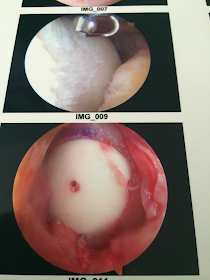

Until this. And where did this come from?! I avoided all the regular injuries and out of nowhere after having the best triathlon of my life at Ironman Florida 2012 I come down with a freak severely damaged knee, yet not even the surgeons involved point the finger at the wear and tear that results from running. My femoral condyle cartilage defect was as far from the typical “take two weeks off” prognosis as it gets, and now here I am 8 months and 2 surgeries later without the capability of a jog across my living room. I will have spent 4 months of the last year on crutches or in a wheelchair by the time I get through this.